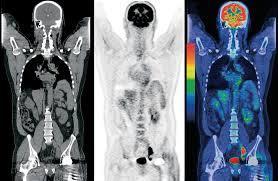

那么什么是PET呢?他的原理又是什么呢?

PET是近年来被广泛提及的名词,现在也在很多中小城市得到普及。很多老百姓都认为虽然花钱多一点,一次把钱到一万,但是扫一下就可以知道全身上下的毛病,还是相当划算。很多有钱人甚至经常进行PET检查,很多患者也主动要求我给其进行PET检查。

PET看的是组织的代谢。也就是说,通过异常的代谢来判断全身上下是否有病变,其中最敏感的要属肿瘤性病变,因为肿瘤的特点就是代谢旺盛。但是PET也存在相当的局限性,首先就是扫描层面的问题,扫描整个人,层面相对比单独扫一个器官要粗略很多,一些细小的问题可能被忽略。然而很多良性疾病,代谢改变不大,在PET扫描的时候也不会被发现。

另外,即使看到病灶,由于扫描的精确度问题,也仅仅可以定位病灶的存在,对于其具体性质还需要进行进一步的专项扫描。